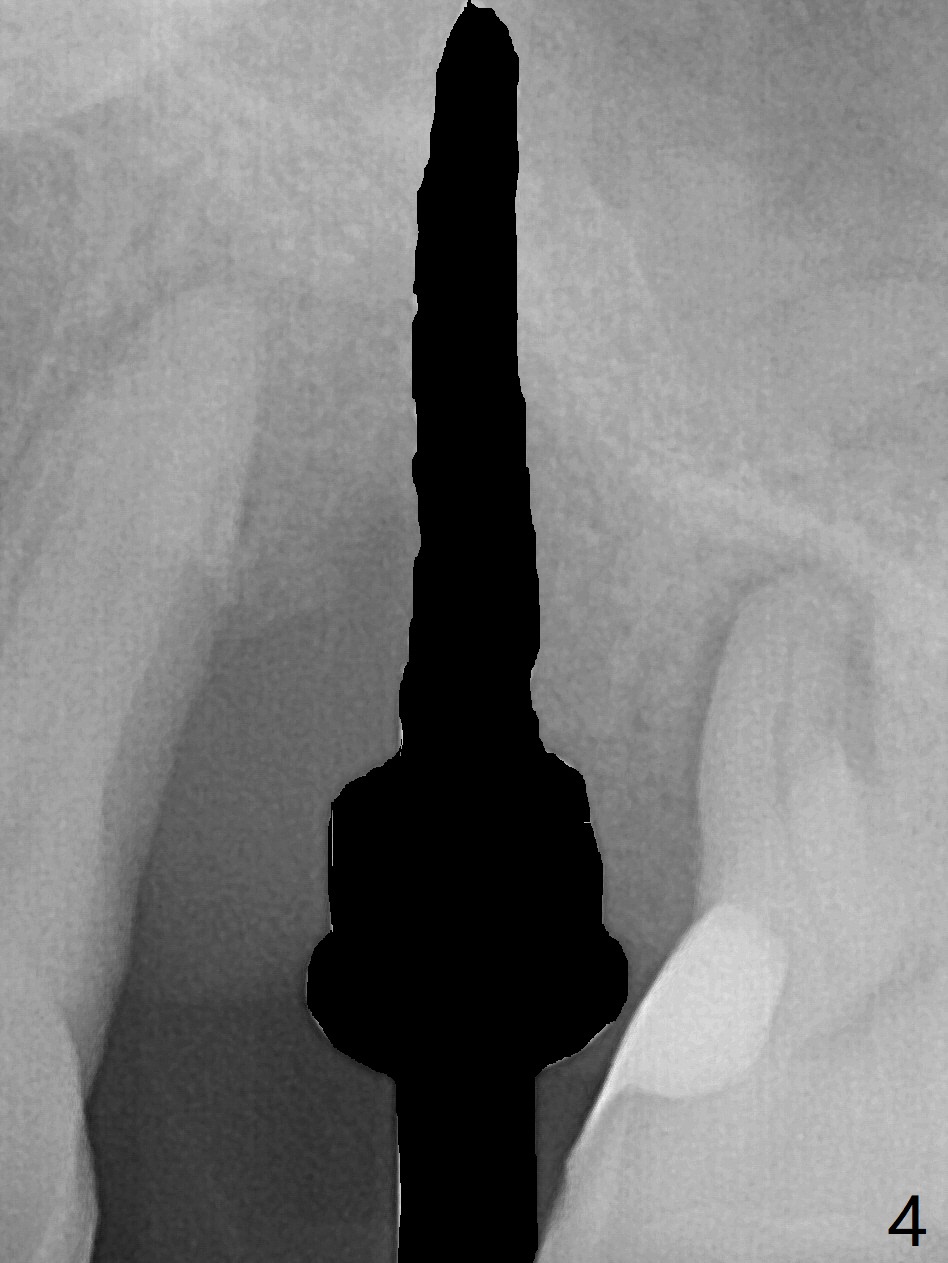

There is more bone apical to the residual root at #13 (Fig.1 red line). An immediate implant along the long axis of the root can be longer, 11.5 mm, favorable for primary stability (Fig.2 (CT taken immediately preop)). The initial trajectory is not ideal (Fig.3). When the pointed/Lindamann bur is removed (Fig.4), effort is made to move the apical end of the osteotomy distal (Fig.5 red arrow) by removing the apical bone (red dashed line). Following sequential osteotomy, a 4x10 mm dummy implant is placed with the trajectory remaining not so ideal (Fig.6,7). As the dummy implant is removed (Fig.8), a new osteotomy is established distal to the existing one (Fig.9). Subsequent drills gradually shift into the original osteotomy (Fig.10 red arrow). When the same dimension dummy implant returns, the trajectory improves with decreased stability (Fig.11). It seems reasonable to place a larger implant without further osteotomy. After placing PRF membrane and Vanilla graft for sinus lift (Fig.13 *), a 4.5x10 mm definitive implant is placed with loss of control in the trajectory (Fig.12,13).